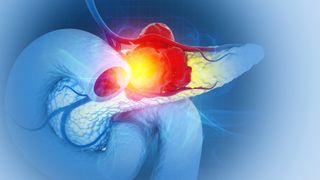

By targeting three key growth pathways at once, researchers eliminated pancreatic tumors in multiple mouse models and prevented the cancer from returning, a promising step toward overcoming treatment resistance.

By Nicoletta Lanese published